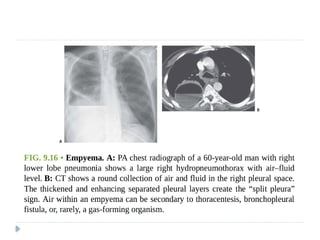

 Empyema:

 Is pus in the pleural cavity.

 The diagnosis is made when the pleural fluid is obviously purulent

 when organisms are identified in the fluid, or when the fluid has an

elevated white blood cell count

 is usually either parapneumonic or postpneumonic.

effusion and pleural empyema

 Empyemas usually:

 form an obtuse angle with the chest wall

 unilateral or markedly asymmetric whereas pleural effusions

usually bilateral and similar in size .

 Biconvex , whereas pleural effusions are concave in shape

towards the lung.

 Features suggestive of an empyema on CT include:

 Enhancing thickened pleura ( split pleura sign) whereas

pleural effusion has thin imperceptible pleural surfaces

 locules of gas absent unless recent thoracocentesis

 Obvious septations

 Associated consolidation

 Associated adjacent infection (e.g. subdiaphragmatic abscess)